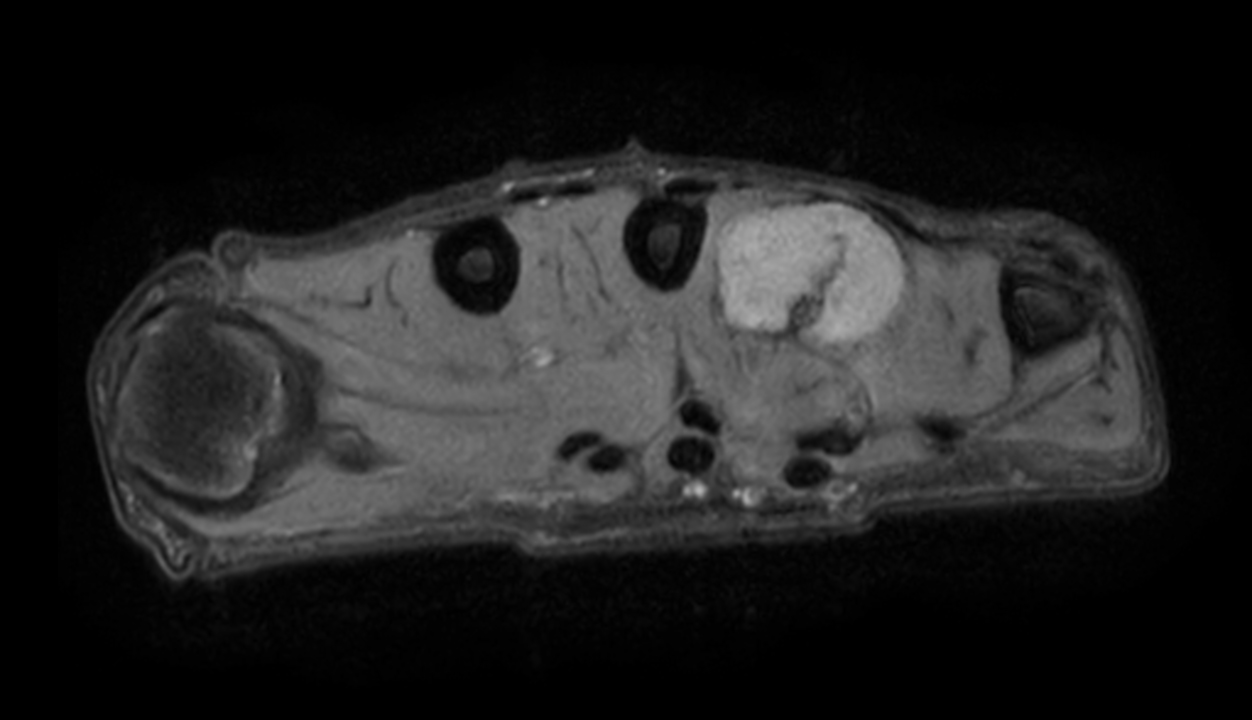

Axial PDw mDIXON XD TSE (Water only)

Axial PDw mDIXON XD TSE (In Phase)

Axial PDw mDIXON XD TSE (Partial FatSat)